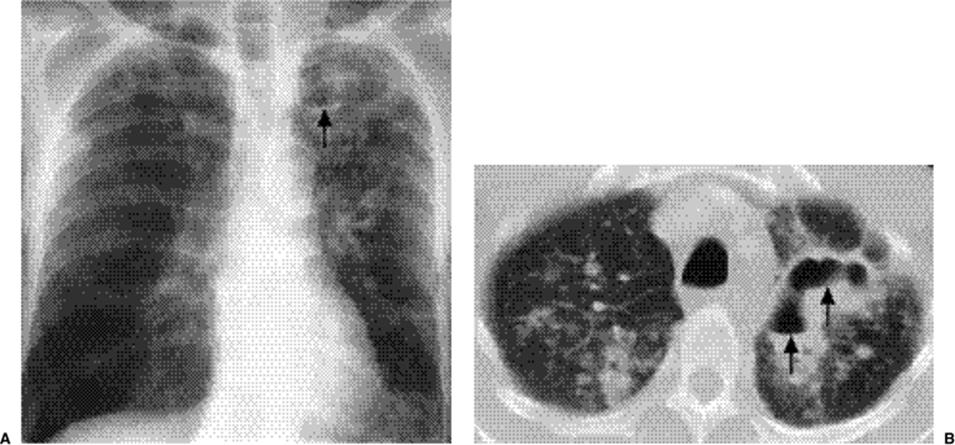

Cavitating consolidation (Figs. 5.13 and 5.14) suggests bacteria or fungi. S. aureus, Klebsiella, anaerobes, and Mycobacterium tuberculosiscommonly cause cavitation. Pneumatoceles may result in a similar appearance (Fig. 5.15) and suggest S. aureus or S. pneumoniae.Emphysematous bullae within consolidated lung may mimic cavities.

Figure 5.14 Cavitary pneumonia (C) at computed tomography.